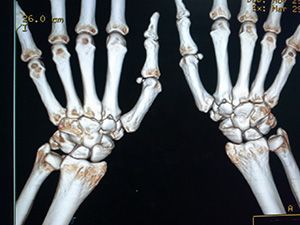

КТ лучезапястного сустава

КТ лучезапястного сустава представляет собой диагностическое исследование кисти, которое выполняется на современном рентгеновском оборудовании — мультиспиральном компьютерном томографе. В отличие от рентгенографических исследований, КТ лучезапястного сустава позволяет выявить патологию уже на ранних стадиях развития.